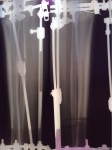

Рентген в 2 месяца.

Сращение идёт отлично, снятие аппаратов в 3 месяца!